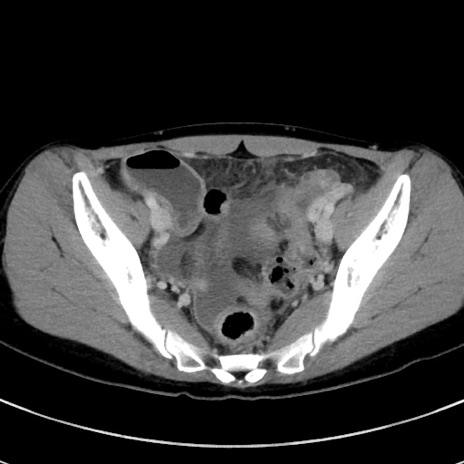

症例17(横断像)

【症例】20歳代女性

【主訴】嘔吐、下腹部痛

【現病歴】昨日夕食後に嘔吐し下腹部痛が出現。本日になっても嘔吐持続し改善しないため来院。

【身体所見】意識清明、BT 37.2℃、BP 108/67mmHg、腹部:平坦、やや硬、下腹部正中から右にかけて圧痛あり、反跳痛軽度あり、tapping pain(+)。

【データ】WBC 13600、CRP 14.94